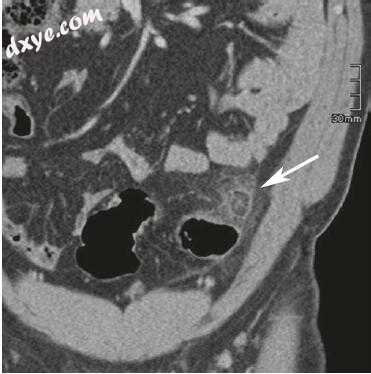

受影响的结肠段可能暗示特定的生物体。例如,志贺氏菌或沙门氏菌的结肠感染仅限于右侧结肠,而CMV和大肠杆菌可见弥漫性受累。淋病,疱疹病毒和沙眼衣原体通常涉及直肠乙状结肠区域(图19.11)。

缺血性结肠炎是患有动脉粥样硬化疾病,低血压或心力衰竭的老年患者的疾病。 血管功能不全和缺血可导致结肠的继发性炎症。 低流量状态和非闭塞性血管疾病是癌(箭头)。 (b)直肠的轴向T2加权图像显示由粘膜下层的高信号,水肿性增厚引起的壁分层,表明炎症过程最常见并且通常导致脾弯曲和直肠乙状结肠的脱水区域的缺血性结肠炎。 左结肠比右结肠更容易受到影响。 影像学检查结果是非特异性的,可能包括与粘膜下水肿相关的壁厚增厚。 可能存在目标标志。 急性事件后,纤维化可能导致结肠腔慢性狭窄(图19.13)。

图19.11(a,b)模拟直肠癌的直肠梅毒。 (a)对比增强的轴位CT图像显示大的圆周肿块 - 像直肠结构,软组织密度提示直肠